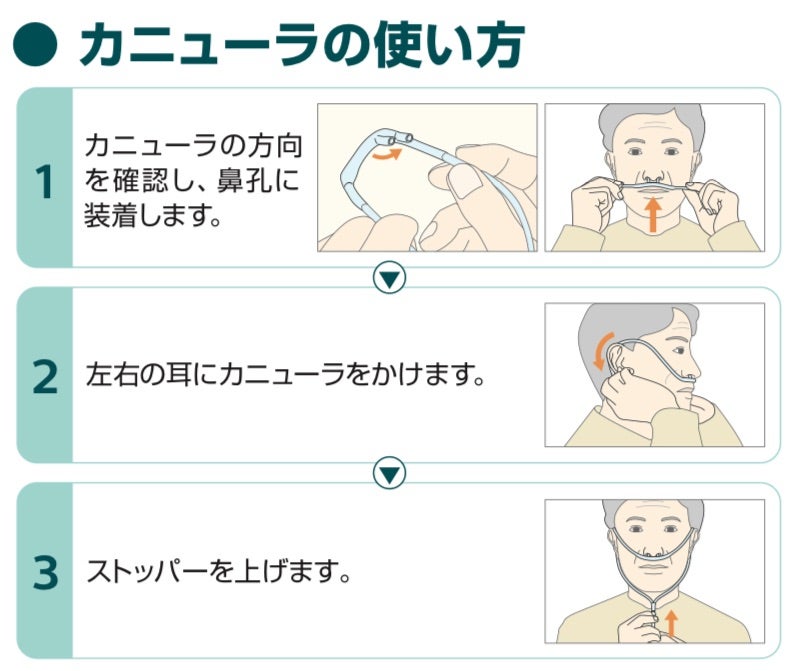

○ カニューラの使い方。

在宅酸素療法で使用する鼻カニューレの装着方法と長時間使用の工夫 - 神戸きしだクリニック 神戸市中央区。

在宅酸素療法で使用する鼻カニューレの装着方法と長時間使用の工夫 - 神戸きしだクリニック 神戸市中央区。

在宅酸素療法で使用する鼻カニューレの装着方法と長時間使用の工夫 - 神戸きしだクリニック 神戸市中央区。